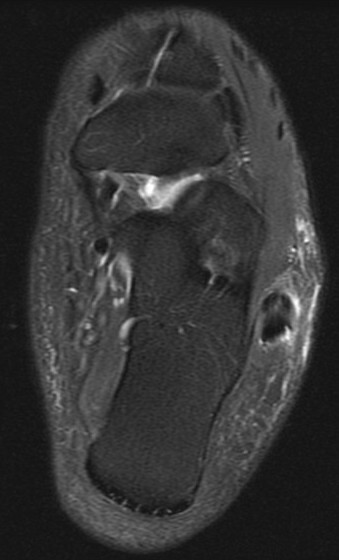

Figure 2 for case Peroneus brevis split tear

Figure 2

41 y/o avid bowler. Nice split tear from the lateral malleoulus tip down past the peroneal tubercle. Reactive tenosynovitis.

Peroneus brevis split tear